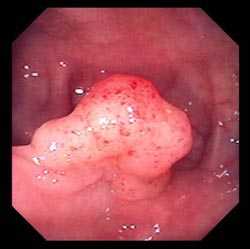

Полип в толстом кишечнике (тубулярная аденома)

Более информативным методом является эндоскопическое обследование, например, колоноскопия . Здесь используется гибкий эндоскоп, который оснащен источником света и различными инструментами, которые позволяют не только осмотреть всю поверхность толстой кишки, но и взять биопсию или провести ряд лечебных или диагностических мероприятий. Например, остановить кровотечение, удалить полип, выполнить хромоскопию — исследовать подозрительный участок с помощью различных световых фильтров, установить стенты для разрешения кишечной непроходимости и др.